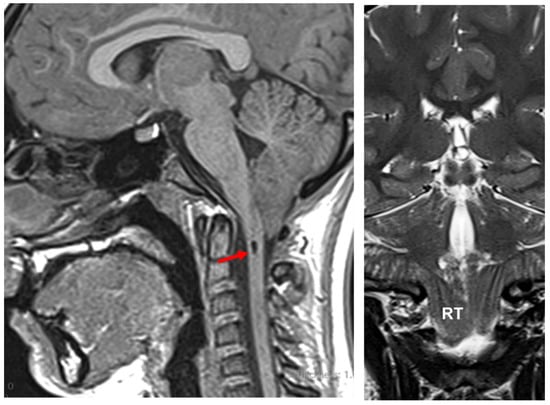

14. The Chiari 1.5 Malformation (CM1.5)